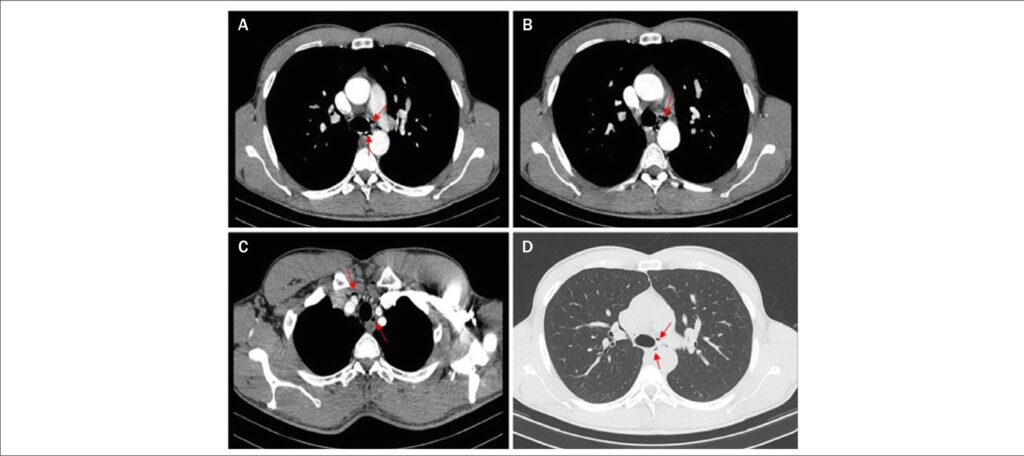

Um atleta do sexo masculino, de 31 anos, apresentou dor torácica aguda, agravada à deglutição, após completar uma maratona. Exame físico e sinais vitais normais. O eletrocardiograma mostrou ritmo sinusal, bloqueio incompleto de ramo direito e onda T negativa em V1–V2. Análise de sangue com valores normais de dímeros-D e pequena elevação da troponina-I (máximo em 72 horas: 0.52 ng/mL; normal <0.07 ng/mL), com níveis oscilantes. Radiografia de tórax, ecocardiograma e coronariografia normais. Realizada tomografia computadorizada (TC) cardíaca, revelando pequenas coleções gasosas no mediastino superior e médio compatíveis com pneumomediastino espontâneo (PS). ( and )

PS é uma entidade rara, geralmente benigna e frequentemente subdiagnosticada. O exercício físico intenso é uma causa reconhecida. A TC avalia a extensão, os fatores causais/patologias e revela o diagnóstico quando a radiografia de tórax é normal.